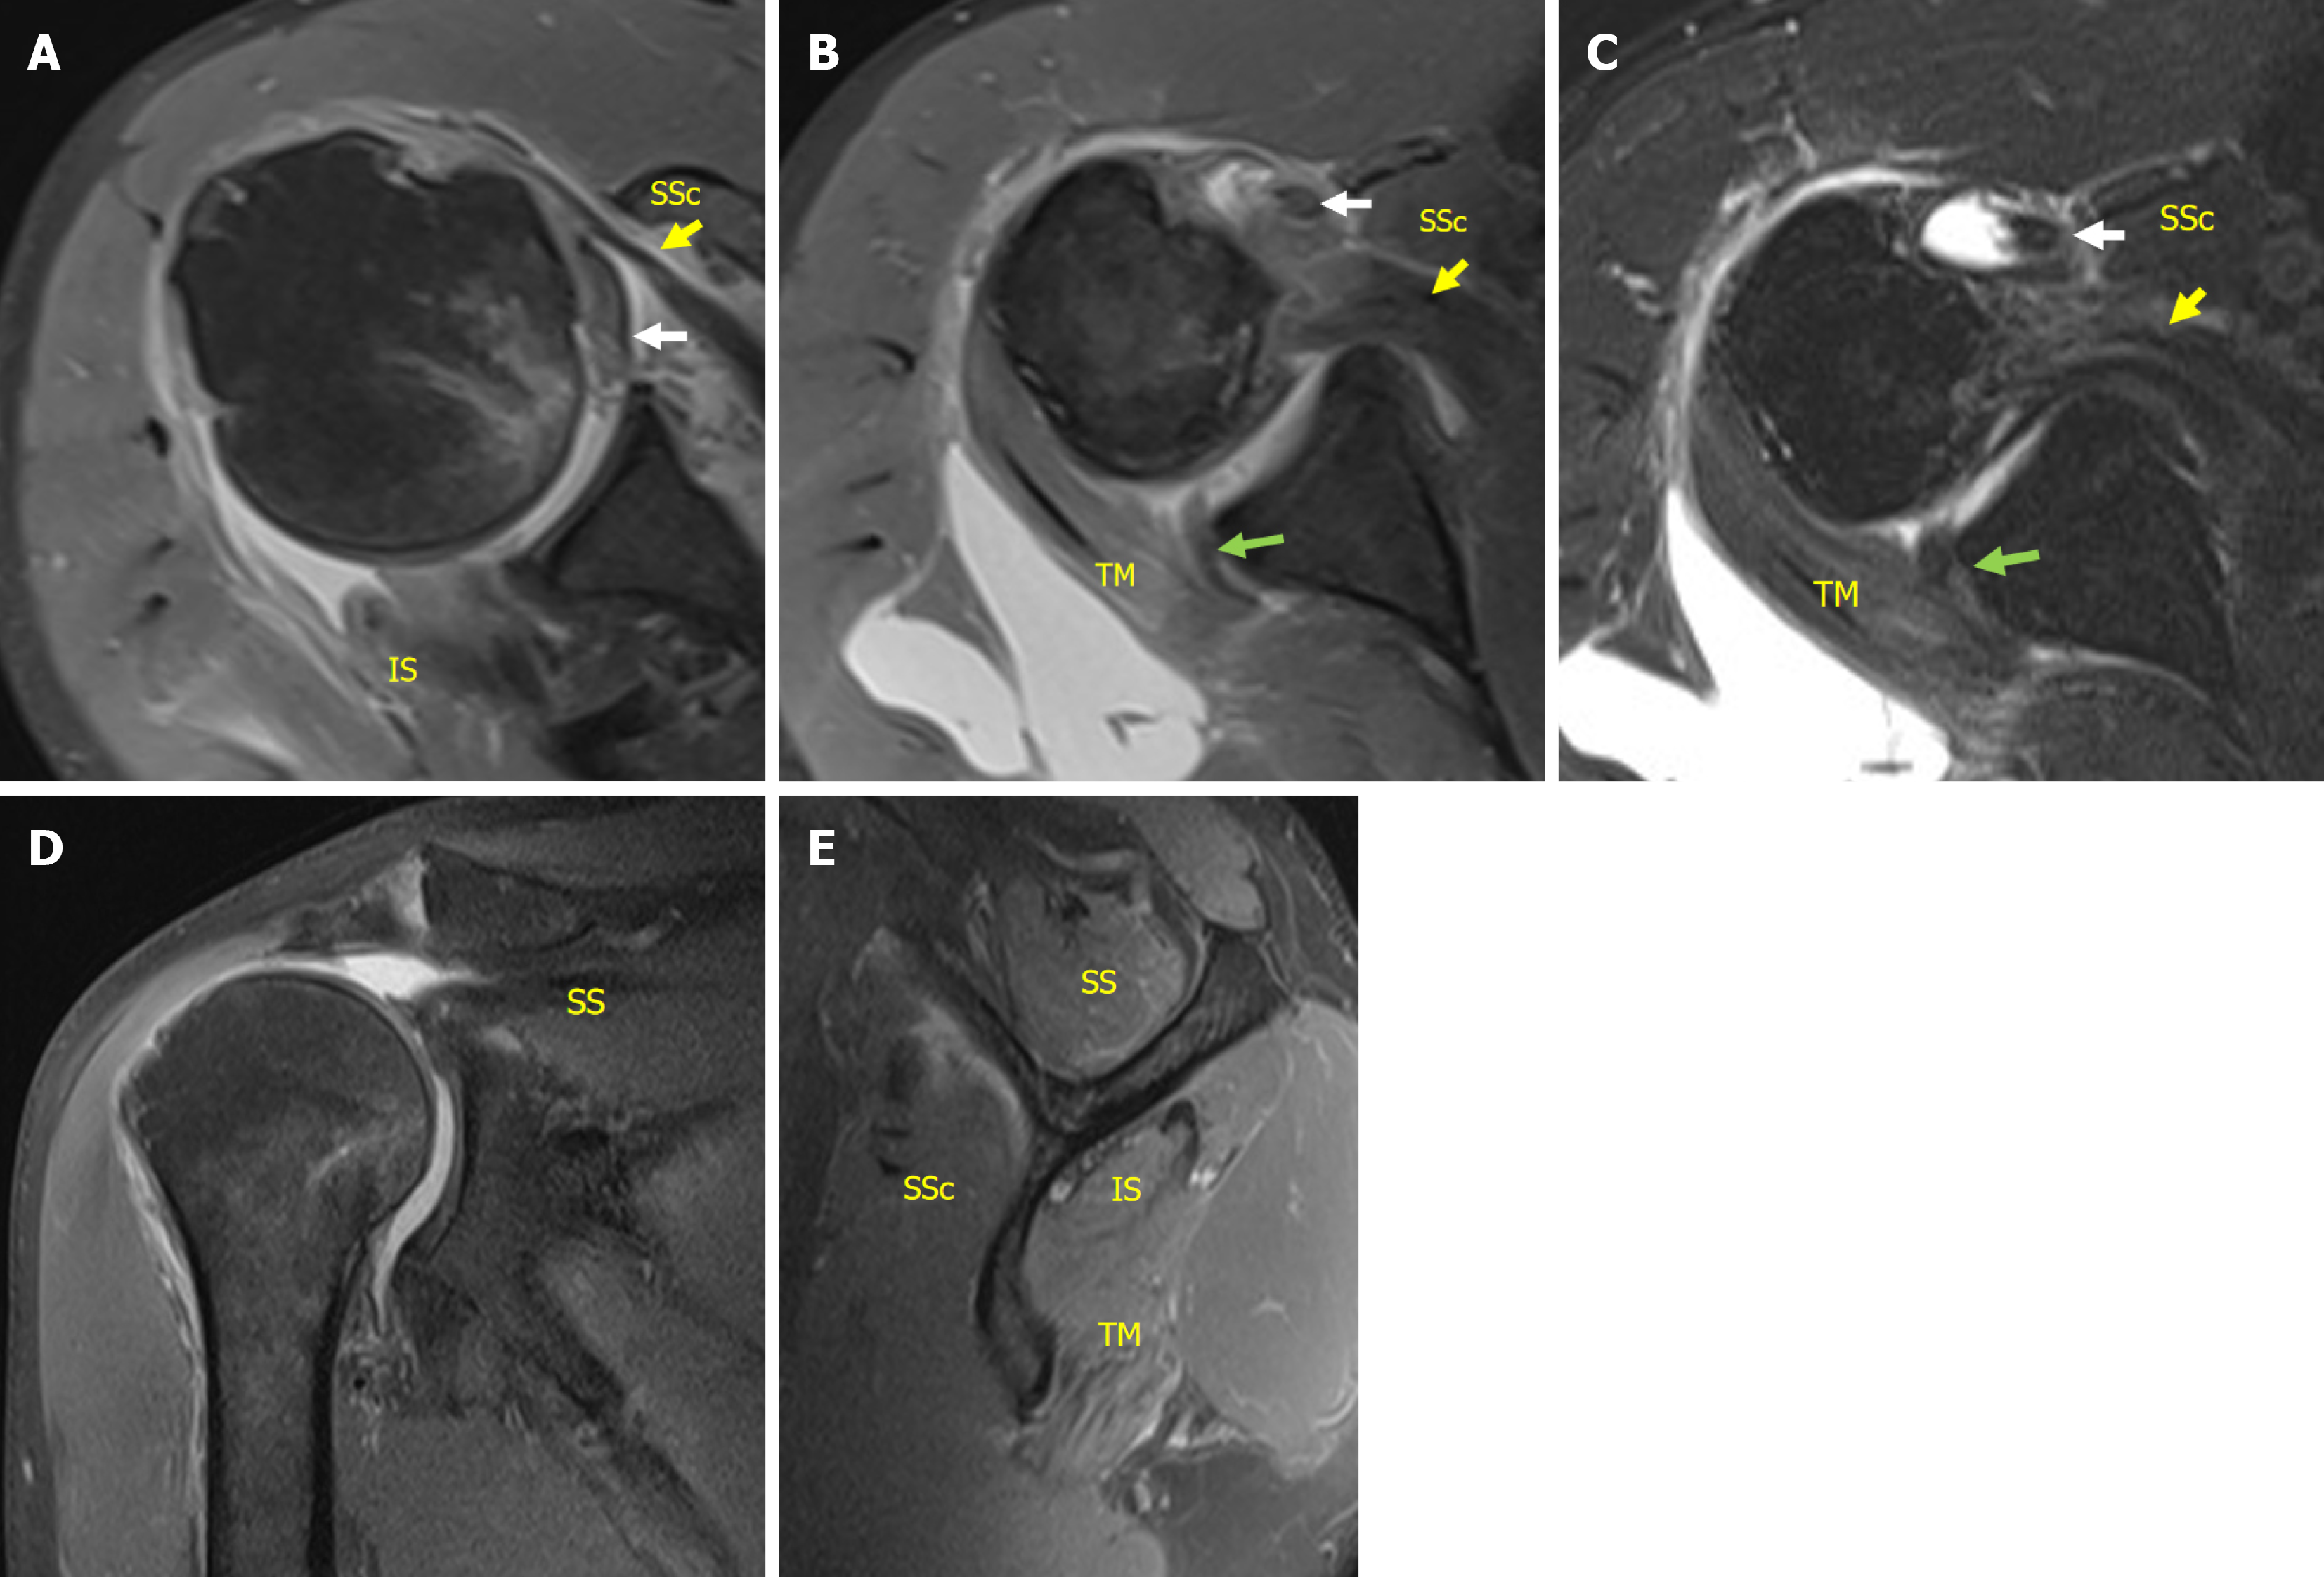

Figure 3 Magnetic resonance imaging performed 2 weeks after the injury.

A-C: Images revealed complete tear of infraspinatus tendon and an upper two-thirds complete tear of the subscapularis tendon (LaFosse stage 3) as well as medial dislocation and rupture of the long head of the biceps tendon. The posterior-inferior labrum was torn but remained attached to the scapular periosteum and partially to the glenoid. Glenoid bone loss was minimal; D: Complete tear of supraspinatus tendon with retraction to the glenoid (Patte stage 3). The rotator cuff tear was classified as the most severe topographic type (involved segment 6 in the sagittal plane); E: Fatty infiltration was mild (Goutallier grade, supraspinatus/infraspinatus/subscapularis/teres minor: 2/1/1/0). White arrow: Long head of the biceps tendon; Yellow arrow: Subscapularis; Green arrow: Posterior-inferior labrum; SSc: Subscapularis; SS: Supraspinatus; IS: Infraspinatus; TM: Teres minor.